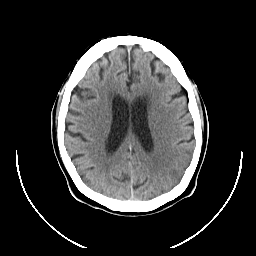

CT Study #1 -- Slice #18